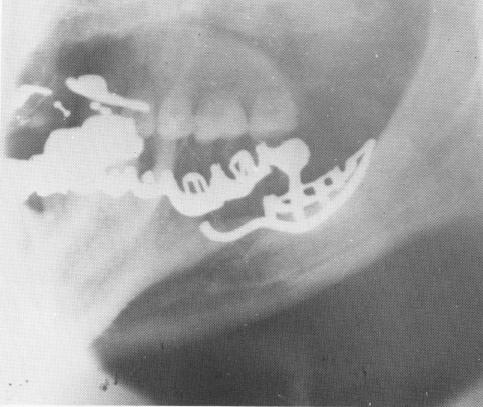

After the elastic set, the two pins were pulled out of the impression in a labial direction so that the impression could be removed without tearing the material. The two pins were then immediately re-placed into the elastic impression (Fig. 12-89). A surgical wax interocclusal centric relation bite and an alginate impression of the lower arch of teeth were also taken.

A master investment model was poured into the elastic impression with the seated fixation pins (Fig. 12-90), and the subperiosteal framework was waxed up directly on the model. It was then cast after the fixation pins were removed (Fig. 12-91).

Fig. 12-99. Periapical intraoral x-rays of five different cases utilizing the unilateral subperiosteal implant as the posterior abutments. These cases with the lingual fingers have been in the mouths of these patients from 7 to 12 years. A shows a 12-year postoperative radio-graph.